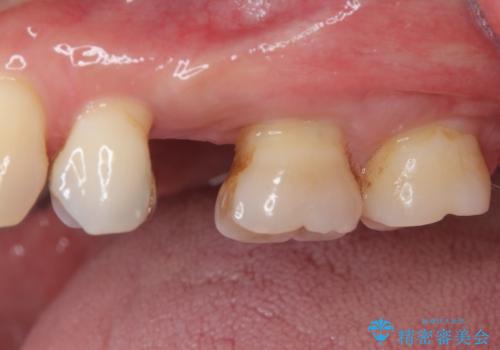

インプラント埋入時に十分な安定性が確認できたため、当日仮歯を装着しました。

埋入から2ヶ月ほどでインプラントの十分な生着が認められ、処置した歯肉も綺麗に治癒したため、速やかに補綴治療を行いました。